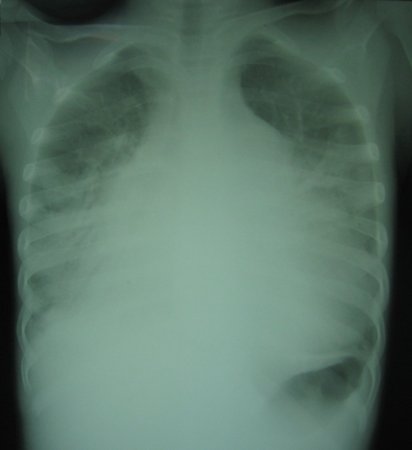

Radiografia torácica de insuficiência cardíaca biventricular ocasionada por cardite aguda na febre reumática

Lancet. 2006 Jun 24;367(9528):2118; usado com permissão